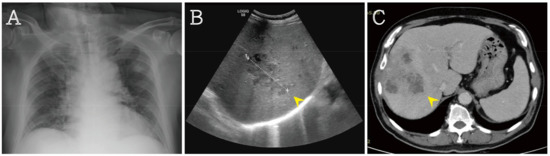

The chest X-ray revealed bilateral pulmonary infiltration with air bronchograms. The abdominal echo showed multiple poorly demarcated lesions with a predominantly hypoechoic appearance. Gas bubbles were seen in the liver lesions. Computed tomography (CT) confirmed the diagnosis of liver abscess (Figure 2). A brain CT was done and revealed no infection sign.

Figure 2. (A) X-ray exam revealing bilateral pulmonary infiltration with air bronchograms; (B) abdominal echo showing multiple hypoechoic lesions with gas bubbles (arrowhead); (C) Computed tomography exam revealing several heterogenous lesions in the liver (arrowhead).